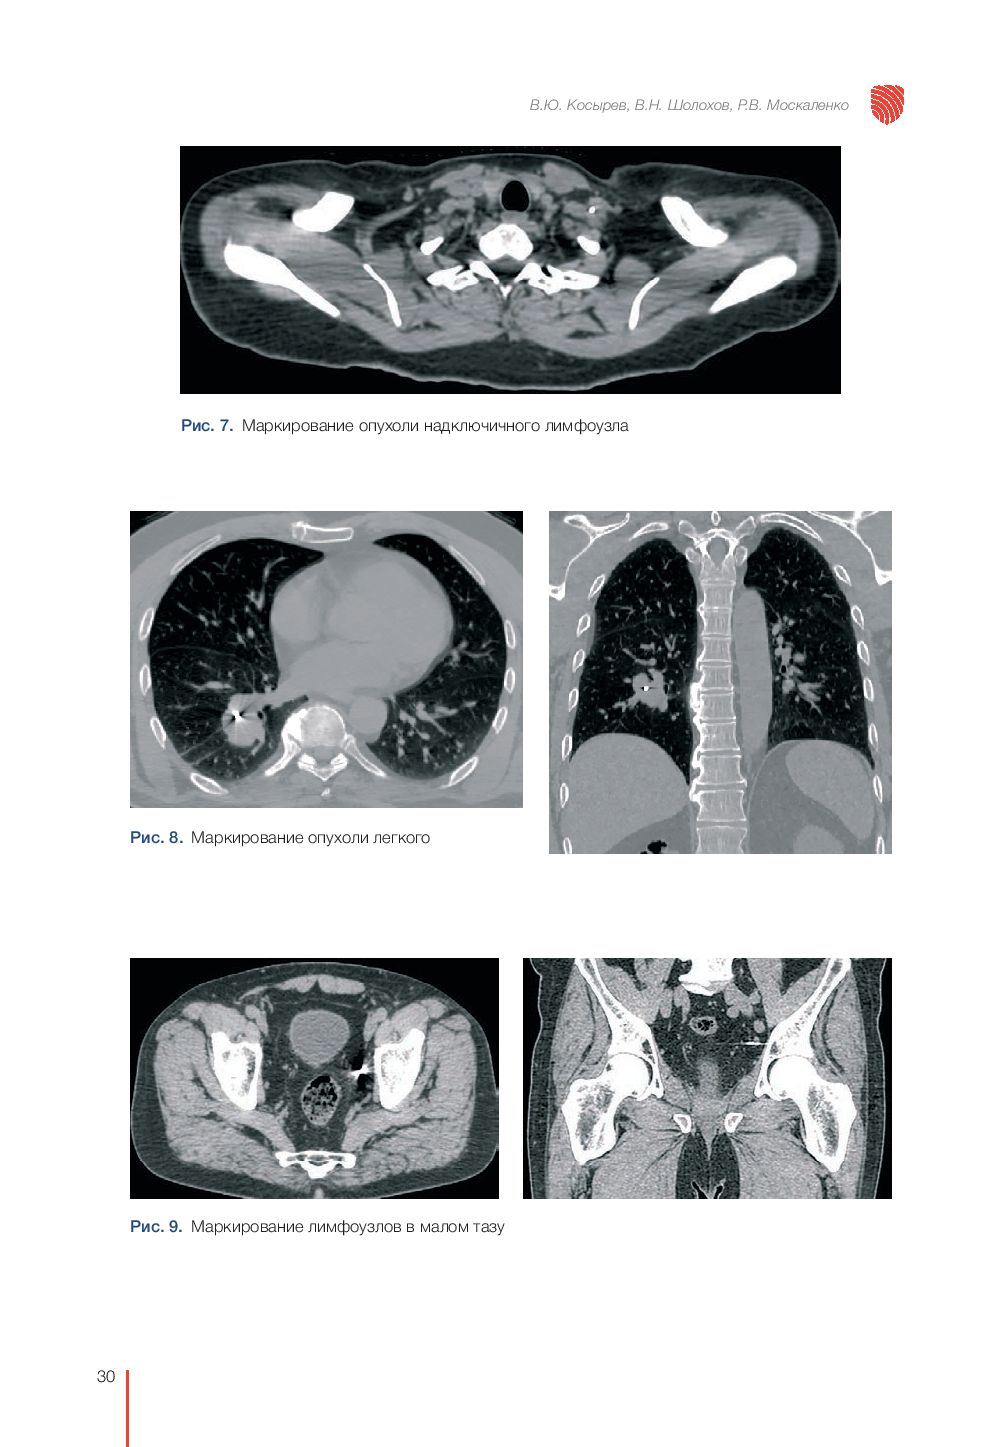

"Рекомендации по проведению стереотаксической лучевой терапии на аппарате "КиберНож" – это подробное руководство по вопросам необходимости применения стереотаксической лучевой терапии при различных злокачественных и доброкачественных процессах. Книга включает в себя детальное описание физико-технических особенностей роботизированной радиохирургической системы "КиберНож" и развернутые рекомендации по использованию аппарата для лечения различных онкопатологий и доброкачественных новообразований. Каждая глава снабжена клиническими примерами и планами лечения.